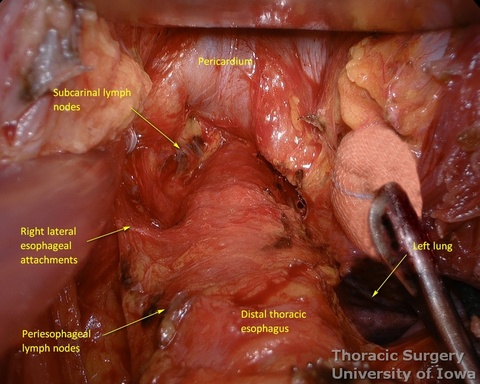

- Esophagus is circumferentially mobilized under direct vision using combination of sharp and blunt dissection up to the level of the carina.

- Right lateral esophageal “ligament” (attachments to the parietale pleura, pulmonary ligaments and branches of vagal nerves) is exposed are divided under direct vision

- Left lateral esophageal attachments (“ligament") is divided under direct vision

- Esophageal arteries (aorto-esophageal branches) and vagal nerves are divided under direct vision using the energy device.

- Periesophageal and subcarinal lymph nodes are dissected separately or en-block with the esophagus under direct vision.

- Use of energy devices should be limited near the membranous portions of the airways.

- Dissection of the distal and mid esophagus is completed using a combination of an energy device and suction tips.